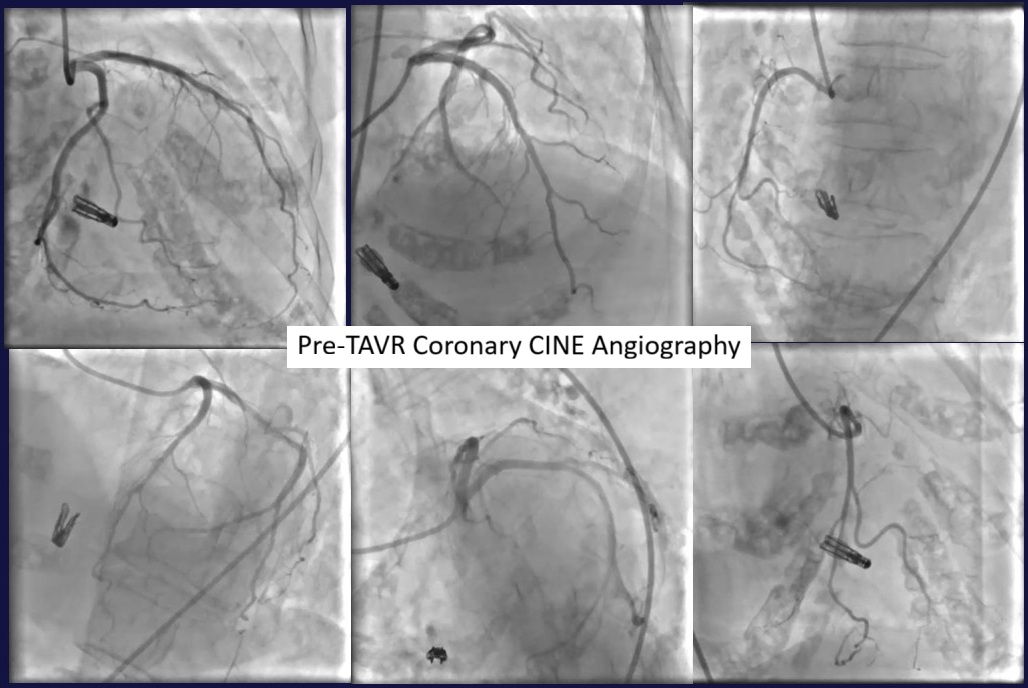

Relevant Catheterization Findings

The patient was performed multimodality of investigations in many medical center, evaluating symptoms. The first, CAG showed non-obstructive CAD. CTA as TAVR protocol identified challenge issue of low LCA ostial (7.6 cm.), low aortic valve calcium, addition to concerning of a-step for pacing control across TriClip. We decide to perform TAVR first, followed by re-evaluating MR and TR. Because intervalvular disturbance may occur in multivalvular heart disease, leading valves' severity misestimation.